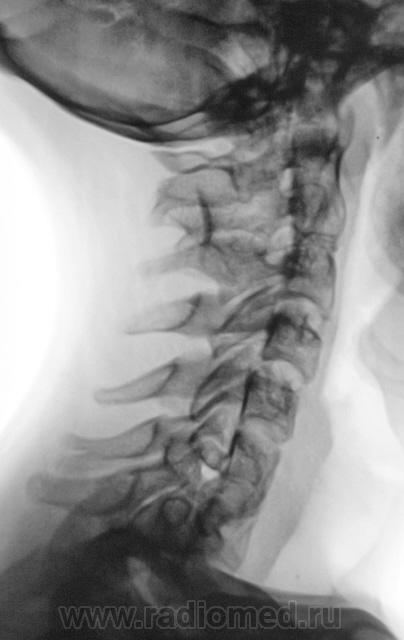

Подросток направлен в рентгеновский кабинет с диагнозом "сколиоз"...

Ну что же, сколиоз есть.

Сколиоз-то сколиоз, но генеза "аномального".

Это синостоз тел верхних шейных позвонков и С6-С7? И боковые клиновидные полупозвонки в верхнегрудном отделе? Это синдром Клиппеля-Файля? А может и Шпренгеля...

Поражает, что только сейчас выявлена такая выраженная дисплазия..там видимо и по органам проблемм хватает..

Совершенно верно. Ведь детей и подростков "смотрят" каждый год. Возникает вопрос, как смотрят и каким "органом"?